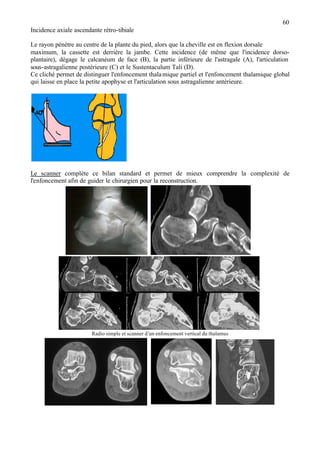

• 70.

70 LES FRACTURES DESMÉTATARSIENS Fracture de la base du 5ème métatarsien C'est la fracture la plus fréquente. Elle est provoquée par une inversion brutale (marche en terrain irrégulier). Le court péronier latéral arrache son insertion sur la styloïde du métatarsien. La douleur est localisée au relief du 5ème méta. La radiographie montre un trait perpendiculaire à l'axe de métatarsien. La fracture intéresse souvent l'articulation avec le cuboïde. Si le fragment est plus gros, c'est l'articulation avec le 4ème méta qui est concernée. Traitement des fractures des métatarsiens - La plupart des fractures ne sont pas déplacées et une simple contention élastique pendant 3 semaines, suffit. - En cas de déplacement et surtout chez les sportifs, on peut proposer une ostéosynthèse, soit par un haubanage pour les fractures de la styloïde, soit par une petite vis pour les fractures plus volumineuses de la base. Fracture déplacée de l’apophyse styloïde du 5ème méta traitement par broche et petit fil métallique Fracture du 1er métatarsien C’est la plus grave des fractures des métatarsiens, en raison des séquelles possibles sur la statique. L'œdème post-traumatique est important. Si le déplacement est marqué, il est indiqué de faire une réduction chirurgicale et une ostéosynthèse avec un matériel miniaturisé. Les fractures des métatarsiens moyens Elles se situent surtout au niveau des cols ou des diaphyses et sont multiples. Quand elles sont peut déplacées, on les néglige. En cas de déplacement important, et surtout si le 5ème métatarsien, ou le 1er, sont fracturés avec les métatarsiens moyens, on propose une réduction sanglante avec un embrochage centro-médullaire ou des petites plaques. Les fractures de fatigue Elles sont souvent situées au niveau des cols ou des diaphyses et sont multiples. Elles se consolident rapidement en 3 ou 4 semaines. FRACTURES DES PHALANGES Elles sont plus bénignes. Elles résultent souvent d'écrasements par une charge sur les orteils. La fracture est souvent comminutive et ouverte. Le traitement est une contention par un "strapping" adhésif avec les orteils voisins pendant 2 à 4 semaines. LES LUXATIONS MÉTATARSO-PHALANGIENNES sont réduites par traction. Si la stabilité est insuffisante on utilisera l'embrochage par une petite broche. -------------------------------------